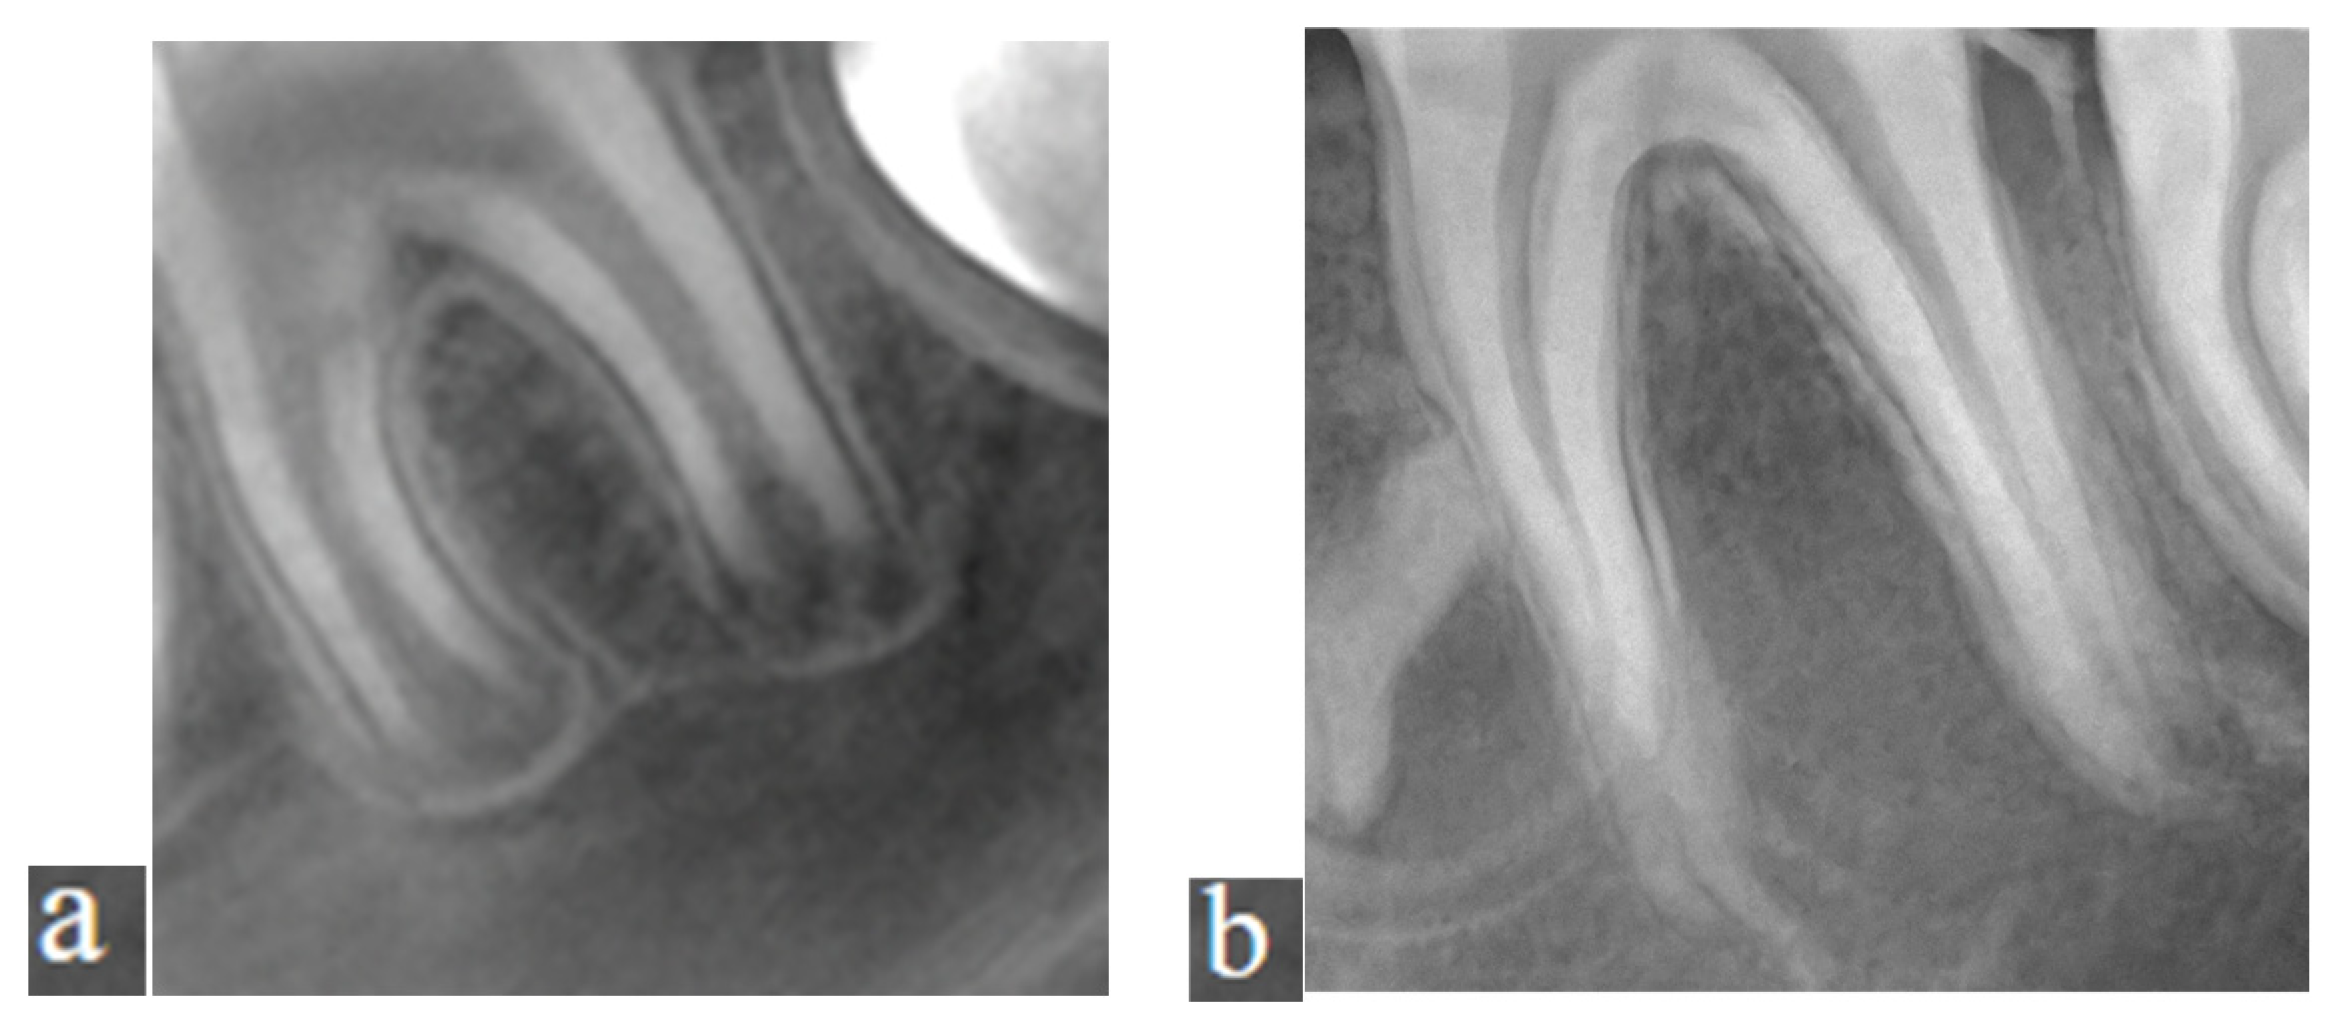

For standardization, the cervical region of the lower anterior teeth was used as a reference point. The imaging area was taken with a thickness of 15 mm. The resulting pseudopanoramic radiographs were recorded. A numbering system was used, without mentioning the patient’s name, in accordance with the commitment under the Personal Data Protection Law. Cropped images obtained from these radiographs were included in the study. In the CBCT images, apical closure was assessed in the axial section. According to the Cvek classification, teeth with an apical opening of 1.0 mm or less were considered to have a closed apex. In contrast, those with larger openings were classified as having an open apex [3]. Regions of interest (ROIs) were extracted from the relevant areas, with dimensions ranging from 471 to 1075 pixels, including only the root portion of the permanent first molar teeth, using ImageJ software version 1.53 (Figure 1a,b). For the study, cropped images were taken from both open and closed root apex views. ImageJ was used for this purpose. To ensure that the cropped images were standardized, the images were scanned to a 471 × 1075 image size, ensuring that all images contained the anatomical structures planned for analysis. After this, sections were extracted from all pseudopanoramic images using ImageJ at these dimensions.

Figure 1. (a) The ROI of tooth number 36 with an open apex, taken from the pseudopanoramic radiograph; (b) The ROI of tooth number 36 with a closed apex, taken from the pseudopanoramic radiograph.